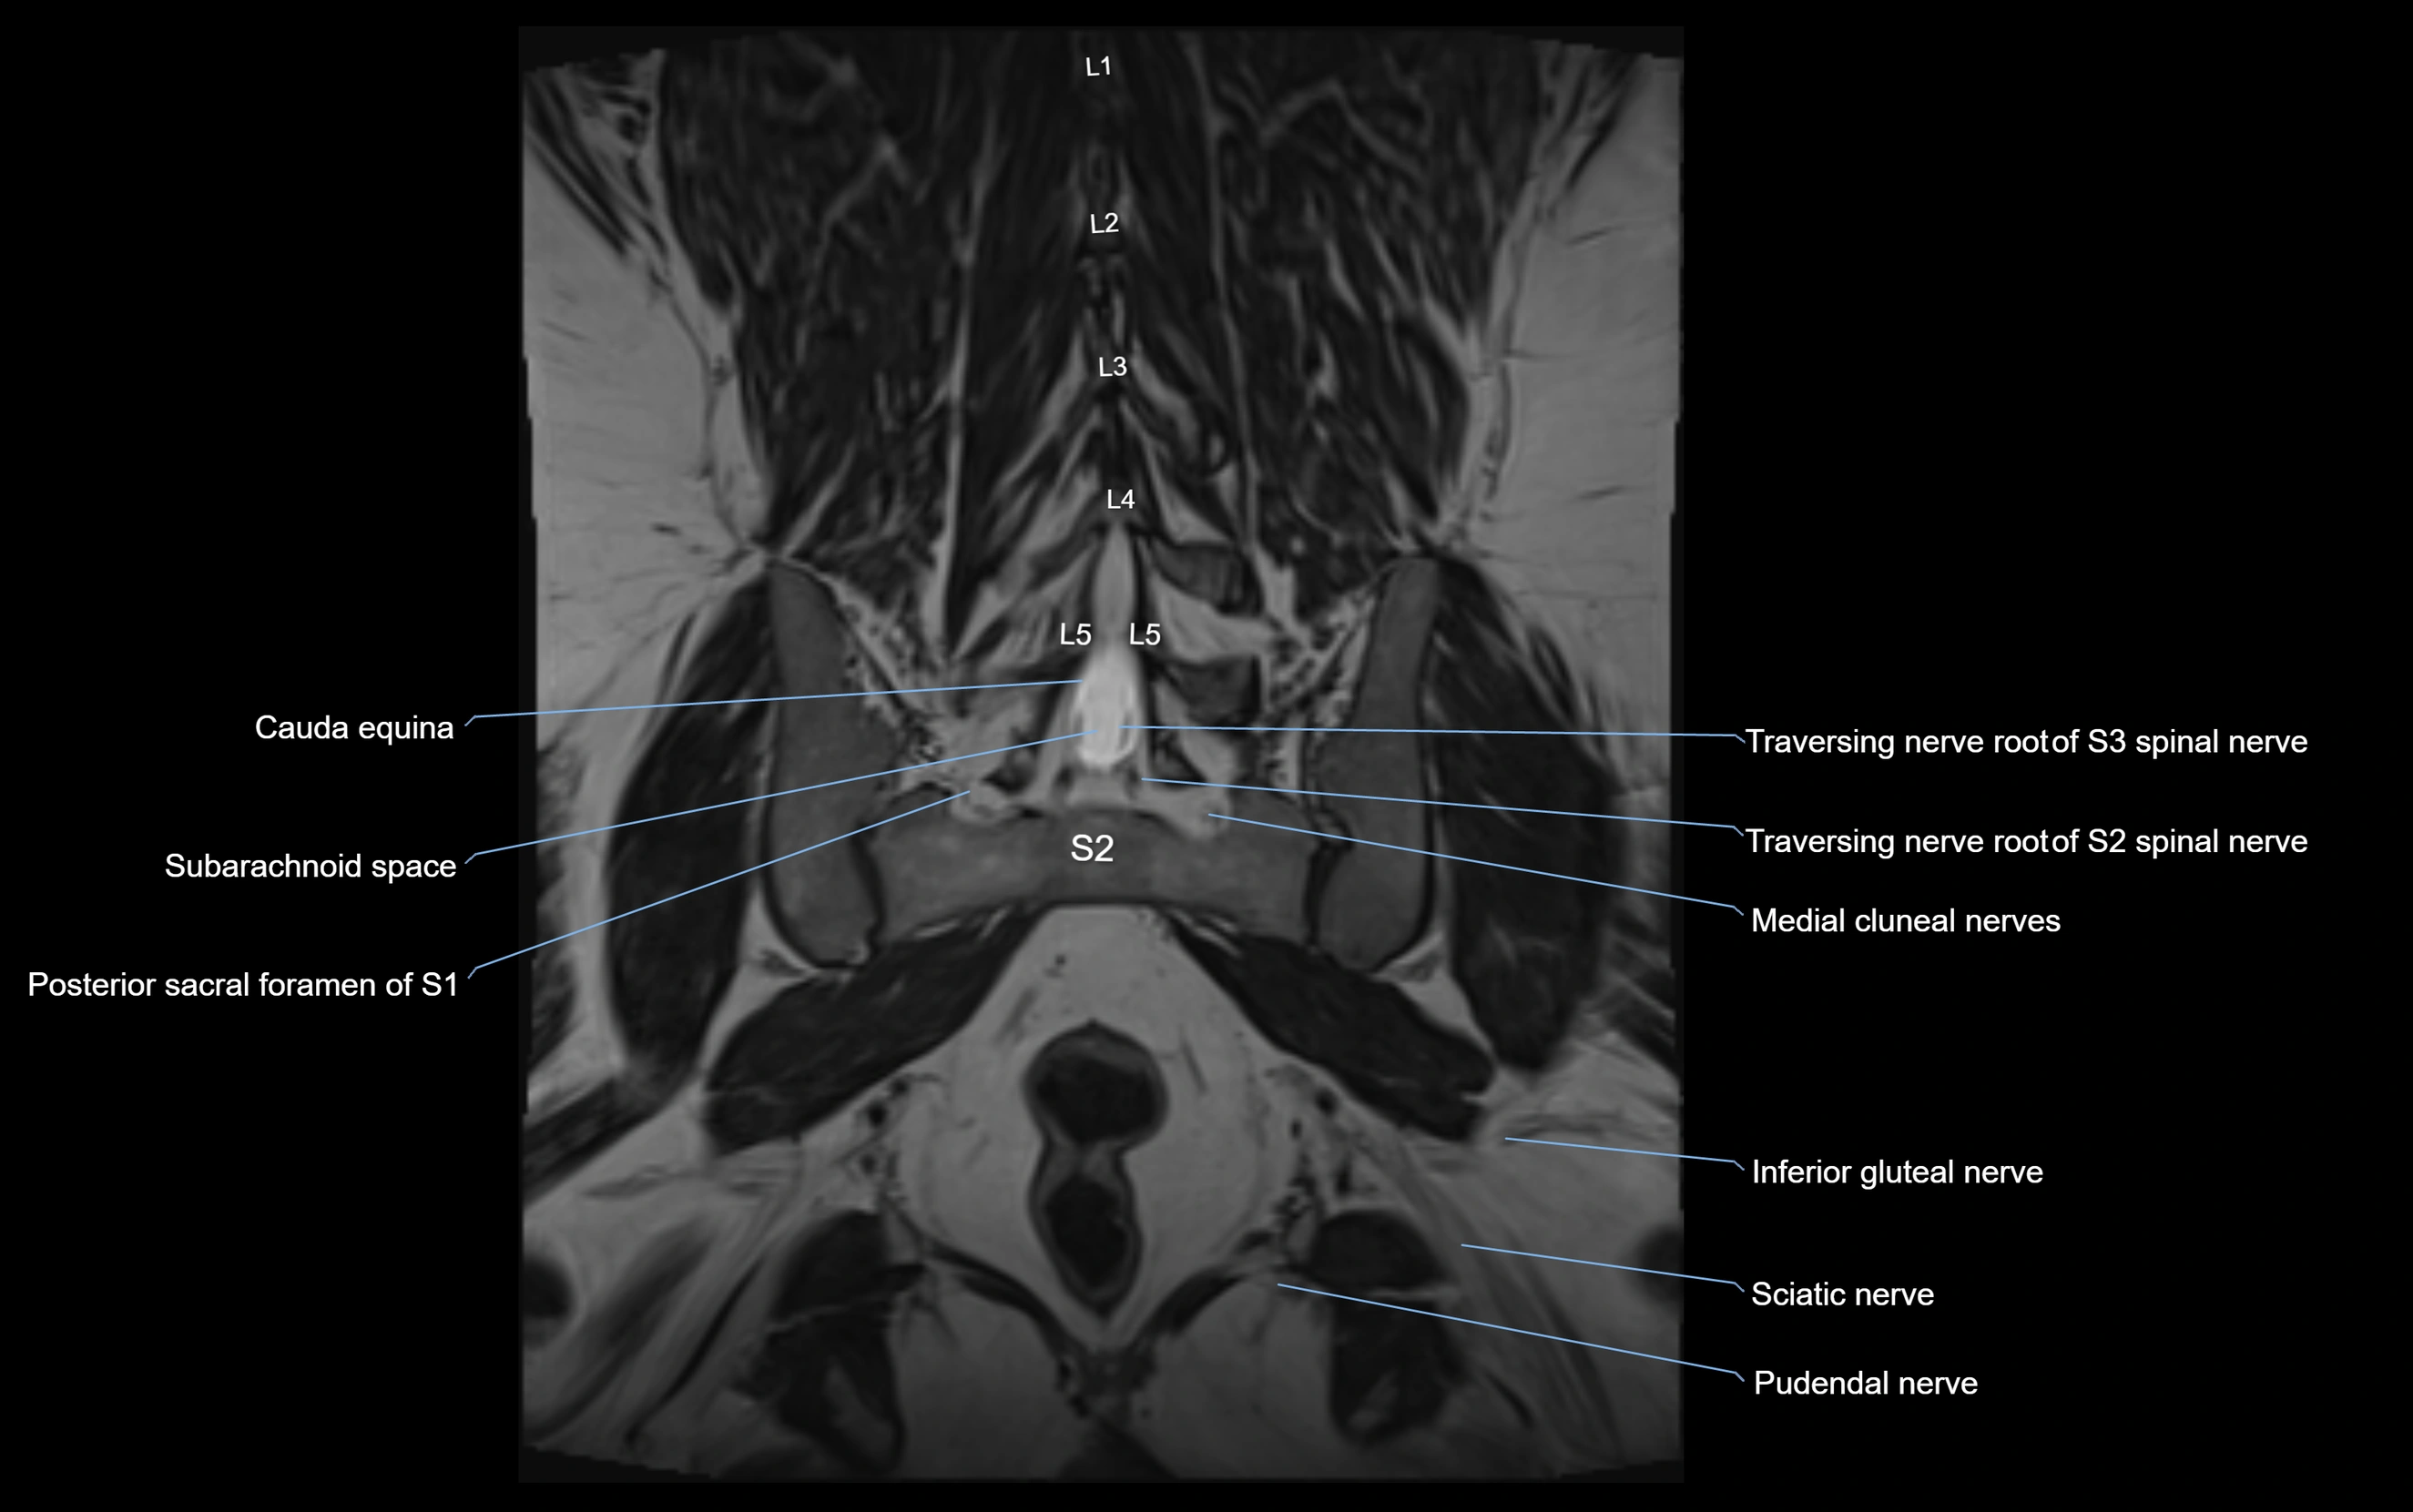

Anococcygeal nerve

The anococcygeal nerve is a small sensory nerve derived from the coccygeal plexus, which itself is formed by the ventral rami of S4, S5, and the coccygeal nerve (Co1). Although tiny, this nerve plays an important role in supplying the skin of the coccyx and the area between the anus and coccyx. It passes through the sacrotuberous ligament and runs in the midline behind the coccyx.

Despite its small size, the anococcygeal nerve is clinically important because of its involvement in coccygodynia (coccyx pain) and perineal pain syndromes.

Origin, Course, and Branches

• Origin:

• Arises from the coccygeal plexus, formed by ventral rami of S4, S5, and Co1

• Course:

• Emerges through the sacrotuberous ligament near the coccyx

• Runs in the midline posterior to the coccyx

• Passes forward into the small space between anus and coccyx

• Branches:

• Small cutaneous branches that supply the skin between the coccyx and anus

Relations

• Anteriorly: Coccyx and sacrococcygeal joint

• Posteriorly: Skin of sacrococcygeal region

• Laterally: Sacrotuberous ligaments

• Inferiorly: Perianal skin and pelvic floor muscles

MRI Appearance

T1-weighted images:

• Nerve appears as a very thin low-to-intermediate signal intensity structure

• Surrounded by bright fat, aiding visualization

T2-weighted images:

• Nerve shows intermediate to mildly hyperintense signal compared to muscle

• Pathological involvement appears brighter

STIR (Short Tau Inversion Recovery):

• Normal nerve appears dark

• Inflamed or entrapped nerve appears bright hyperintense

T1 Fat-Sat Post-Contrast:

• Normal nerve enhances minimally

• Pathologic nerve (neuritis, entrapment, tumor infiltration) shows focal or diffuse enhancement

3D T2 SPACE / CISS:

• Nerve appears intermediate to mildly hyperintense compared to muscle

• Surrounded by bright fat or CSF, improving visualization

• Best sequence for mapping small pelvic nerves such as the anococcygeal